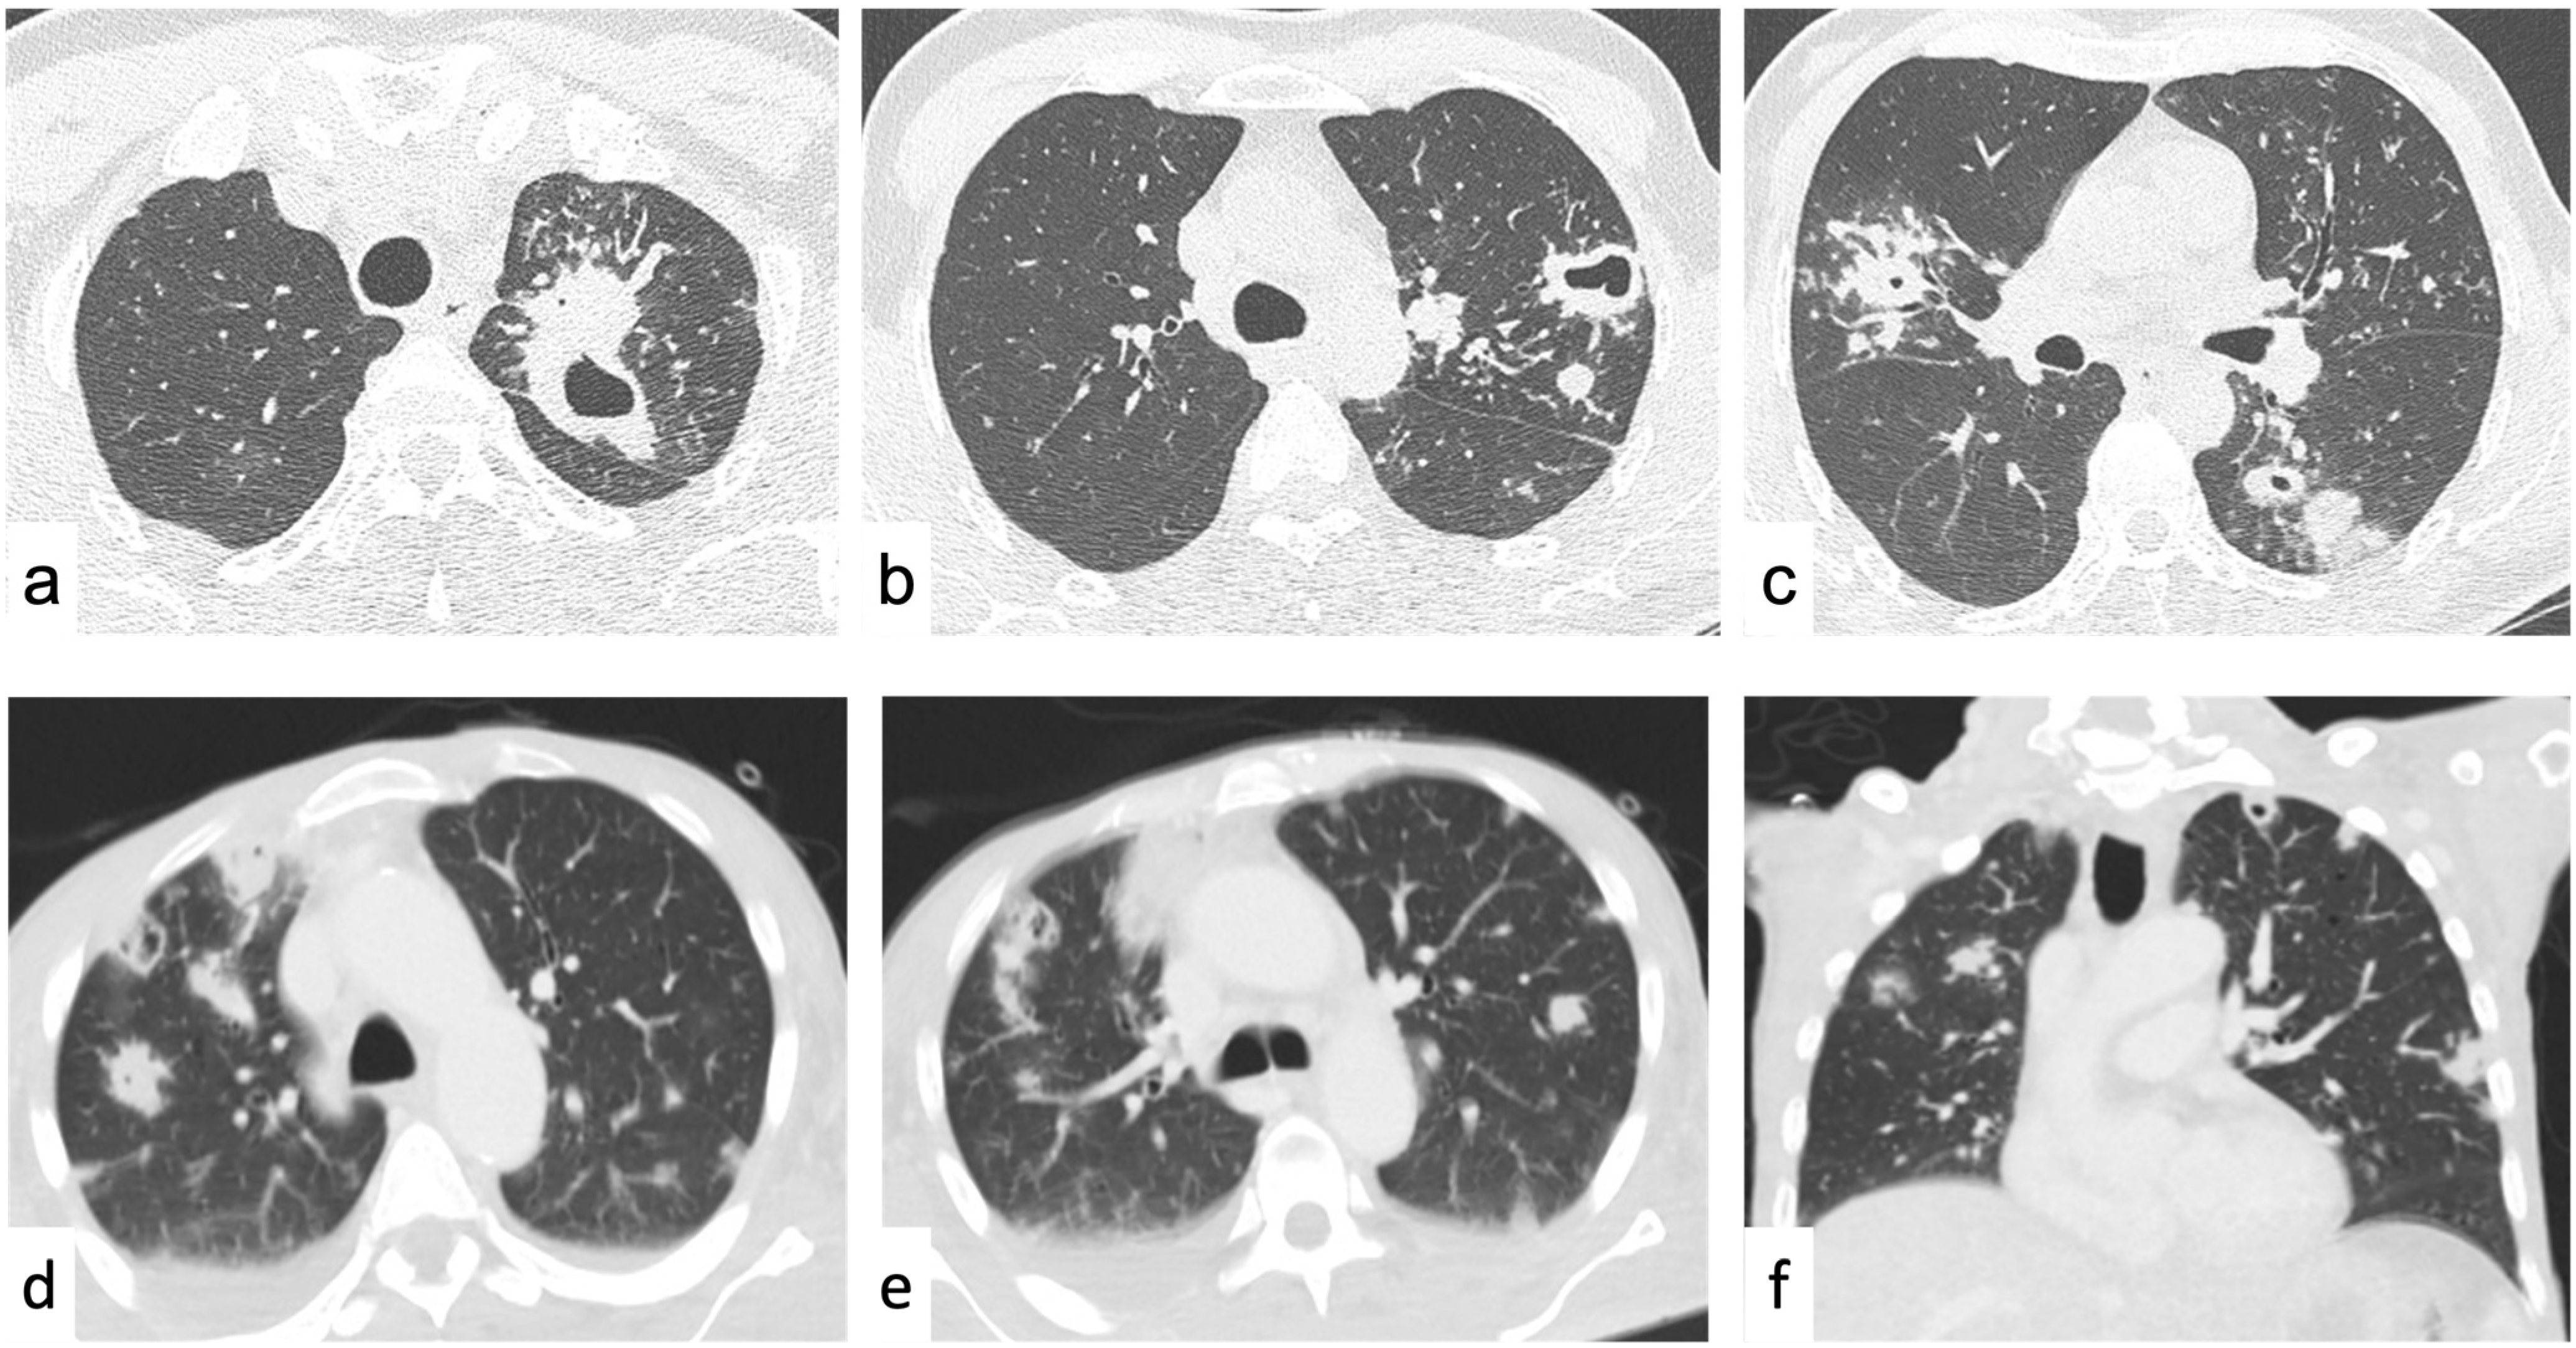

Random Nodules

- Boitsios, G.; Bankier, A.A.; Eisenberg, R.L. Diffuse Pulmonary Nodules. Am. J. Roentgenol. 2010, 194, W354–W366. [Google Scholar] [CrossRef]

- Rossi, S.E.; Franquet, T.; Volpacchio, M.; Giménez, A.; Aguilar, G. Tree-in-Bud Pattern at Thin-Section CT of the Lungs: Radiologic-Pathologic Overview. RadioGraphics 2005, 25, 789–801. [Google Scholar] [CrossRef]

- Palmucci, S.; Inì, C.; Cosentino, S.; Fanzone, L.; Pietro, S.D.; Mari, A.D.; Galioto, F.; Tiralongo, F.; Vignigni, G.; Toscano, S.; et al. Pulmonary Vasculitides: A Radiological Review Emphasizing Parenchymal HRCT Features. Diagnostics 2021, 11, 2318. [Google Scholar] [CrossRef]